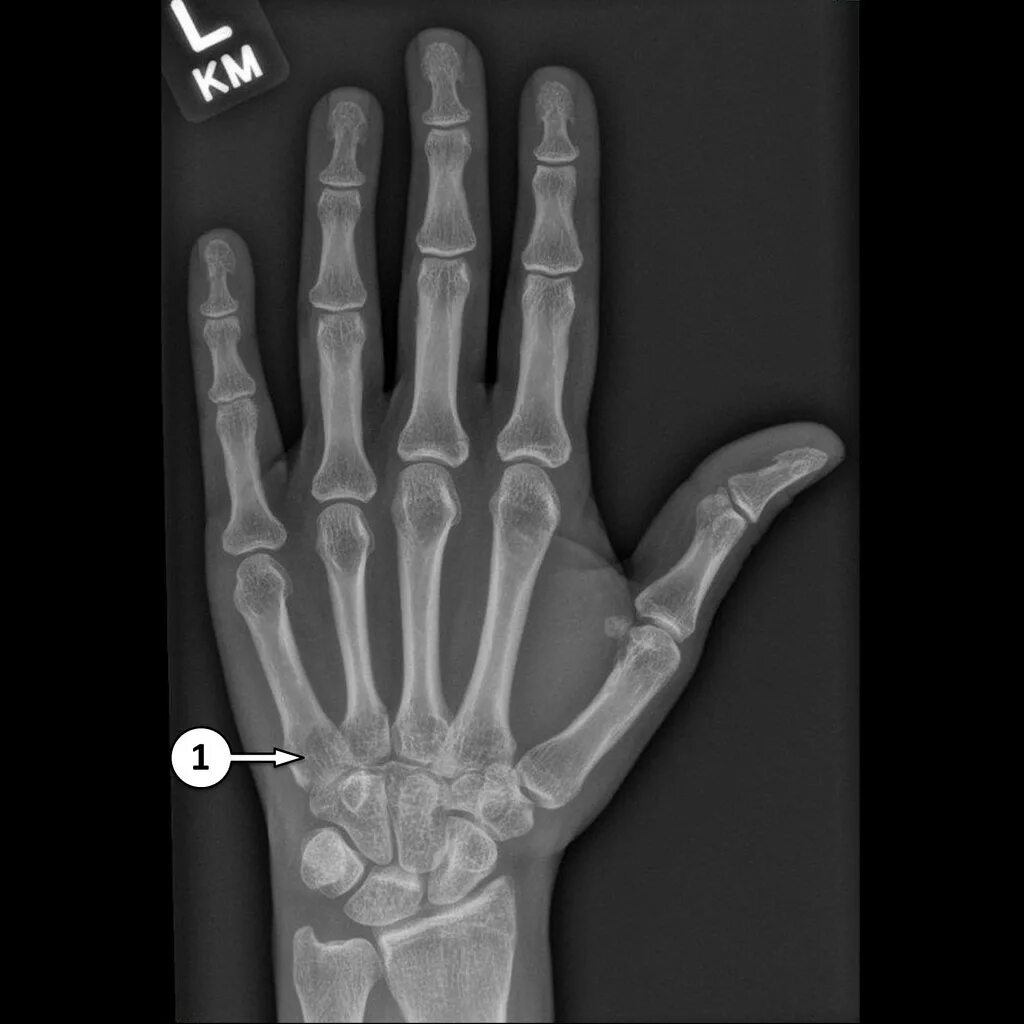

Source x rays